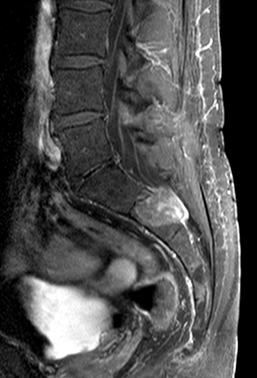

10.2.1.3. MRI:

As opposed to CT examination MRI, thanks to its superior soft-tissue contrast, is excellent for the representation of intraspinal structures. Depending on the magnetic field strength / resolution ability it is a unique imaging method of the spinal chord.

MRI: only MRI can provide a definitive diagnosis by depicting the expanded region within the axis of the spinal chord as an expansile lesion showing liquor intensity on all sequences (weak T1 signal and strong on T2 weighted imaging).

Spinal arteriovenosus malformations (AVM): a rare disease, usually manifesting in early childhood. They can be intradural, extradural and dural in localization – often combined with fistulas.

On MRI its characteristic loss of signal is accompanied by edema in the spinal chord (strong T2W signal).